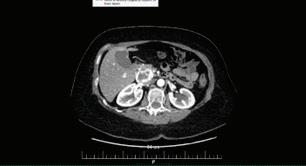

48 КИСТИ НА ПАНКРЕАСАЗНАЧЕНИЕ, ДИАГНОСТИЧНИ ДИЛЕМИ И ИНДИКАЦИИ ЗА ХИРУРГИЯ Н. Шумка, П. Карагьозов

КИСТИ НА ПАНКРЕАСАЗНАЧЕНИЕ, ДИАГНОСТИЧНИ ДИЛЕМИ И ИНДИКАЦИИ ЗА ХИРУРГИЯ

СТР. 48